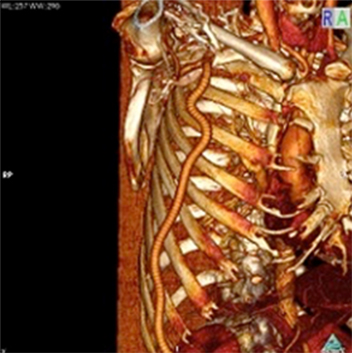

<手術前>両側総腸骨動脈(お腹の中にある足のつけねの動脈)と両側大腿動脈(太ももの動脈)に閉塞、狭窄部位があり、運動障害(間歇性跛行)や皮膚障害(壊死)を引き起こし、車椅子に乗られての入院となりました。

<手術後>右の鎖骨下~腋窩動脈(鎖骨の下から脇の下にかけての動脈)から両側大腿動脈、さらにそこから両側膝窩動脈(膝の裏の動脈)にバイパス手術を施行しました。

運動障害、皮膚障害も改善し、歩いて退院されました。

右鎖骨下〜膝窩動脈吻合

両側総腸骨動脈吻合部

両側大腿動脈吻合部